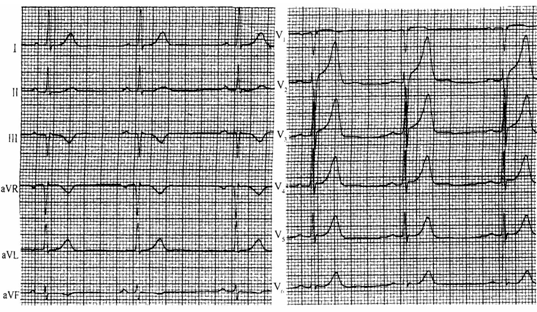

图6 急性心梗超急性损伤期

图7 前间壁心梗

急性心肌梗死:ST段常呈弓背向上抬高,与T波连续形成单向曲线;随后,直立的T波开始倒置并逐渐加深,形成坏死性的Q波;损伤型的ST段抬高和缺血型T波倒置可并存。(特点:弓背向上、动态演变)